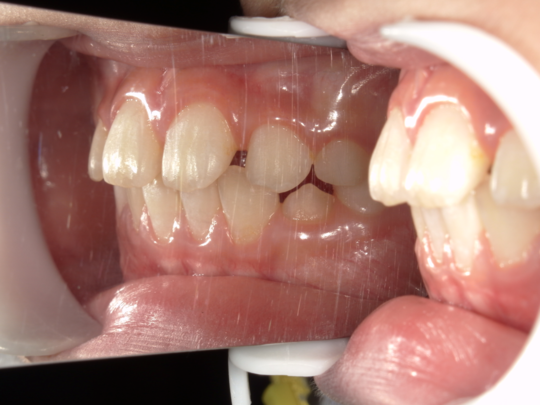

治療前

治療説明 歯科矯正で取り外し可能な矯正方法である床矯正で治療しました

治療期間 4年

治療費用200000 円

治療後

治療の副作用(リスク)歯の動き方には個人差があり、予想された治療期間が延長する可能性があります。。床矯正の使用状況、矯正歯科治療には患者さんの協力が必要であり、それらが治療結果や治療期間に影響します。2次矯正が必要になる場合もあります。